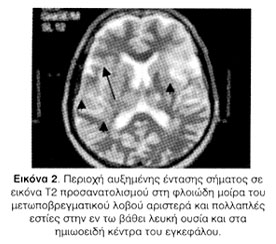

Η μαγνητική τομογραφία εγκεφάλου κατέδειξε πρόσφατη ισχαιμική βλάβη στη φλοιώδη μοίρα του μετωποβρεγματικού λοβού αριστερά και ευρήματα συμβατά με χρόνια ισχαιμική μικροαγγειακού τύπου λευκοεγκεφαλοπάθεια και ανάπτυξη δευτεροπαθούς ατροφίας (Εικόνες 2, 3).